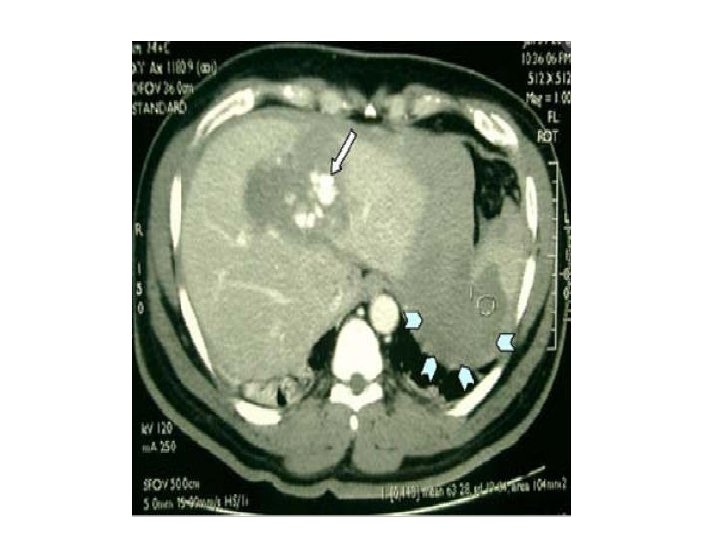

Hemorragia ativa: área focal de atenuação de contraste em fase arterial. Se persistir: falha no tratamento conservador

Tratamento • Graus I – III – Geralmente é clínico (monitorar com hematócrito) • Grau IV – VI (avulsão hepática) – Intervenção cirúrgica no caso de choque e peritonite – Embolização para extravasamento ativo